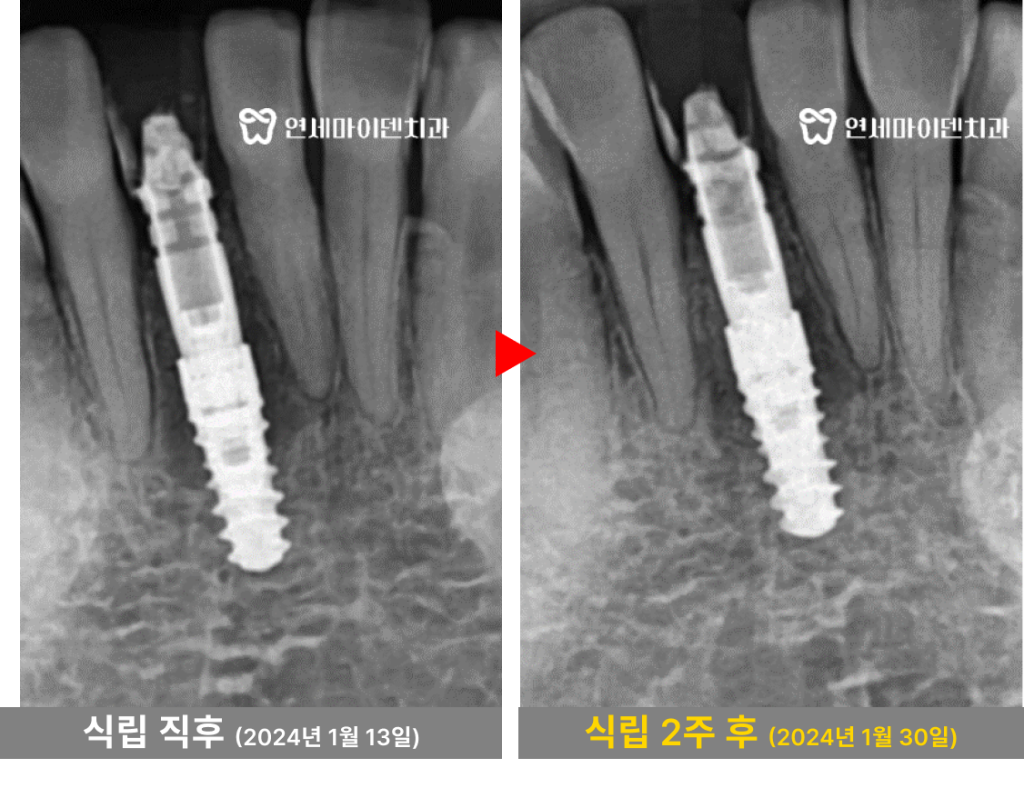

앞니 임플란트 증례: 원데이 발치 즉시 임플란트

안녕하세요, 소중한 치아를 지키는

연세마이덴치과 닥터꼬집 입니다.오늘은 ‘앞니 임플란트‘와 관련된

실제 치료 증례를 소개해드리겠습니다.앞니는 말 그대로 얼굴의 중심에 위치해서

미소와 첫 인상에 직결되는

중요한 치아입니다.하나라도 빠졌을 경우 불편함뿐 아니라

심리적인 위축도 크게 느끼게 됩니다.특히, 치료 과정에서

“앞니 없이 어떻게 지내나요?”

“임플란트가 안되면 어떻게 해야하나요?”

이런 고민을 하시는 분들이 많습니다.이번 사례는 앞니 임플란트를 고민하시는 분들께

현실적인 치료 방향을 보여줄 수 있는 좋은 증례입니다.발치 후 임시치아가 중요한 이유

치료 전 환자분의 상태를 확인했는데,

앞니를 발치한 자리는 공간이 상당히 좁았습니다.무엇보다도 가장 큰 문제는

3개월 동안 임시치아 없이 지낸 점이었습니다.

발치 이후에는 임시치아를 가능한 빨리 장착해야

치조골이 내려앉지 않고 공간도 유지됩니다.하지만, 발치 후 빈 공간을 그대로 놔두게 되면

잇몸 뼈가 흡수되고 잇몸 형태도 무너지게 됩니다.실제로 이 환자분의 경우

발치 부위의 잇몸 뼈가 아직 회복되지 않은 채

엑스레이 상으로 까맣게 흡수되어있는게 보입니다.양옆 치아 뿌리에도 영향을 줄 수 있는 상태였습니다.

당일 임플란트 후 임시치아까지 가능할까?

환자분의 현재 상태를 고려해

양옆 치아를 최대한 건드리지 않으면서

안정적인 임플란트를 심을 수 있는 방법을 계획했습니다.

우선 옆 치아는 가능한 최소 범위만 정리하고

임플란트를 심을 공간을 확보했습니다.이후 뼈가 부족한 부위에는

뼈 이식을 충분히 진행해서 고정력을 확보했습니다.정확한 위치 선정이 중요하기 때문에

3D 네비게이션으로 임플란트 식립 위치를 정확히 계산했습니다.덕분에 좁은 공간이지만 최적의 자리에

앞니 임플란트 식립이 가능했습니다.

또 하나 중요한 것은

임시치아 장착입니다.앞니는 심미적인 부담이 큰 치아기 때문에

발치 당일 임시치아를 장착하는 것이 좋습니다.임시치아를 장착하기 위해서는 고정력이 필요한데,

발치 직후 고정력을 얻기 위해서는

의료진의 숙련된 테크닉이 필수적입니다.다행히 초기 고정력이 잘 확보되었고,

당일 임플란트 식립 후 임시치아 장착까지

하루만에 완성할 수 있었습니다.

식립 2주 후 경과를 확인해보니

치아 양옆의 뼈도 하얗게 잘 차오르고 있습니다.이렇게 발치 후 가능한 빨리 임시치아를 장착해주어야

빠르고 안정적인 회복도 가능합니다.앞니 임플란트 치과, 선택 기준